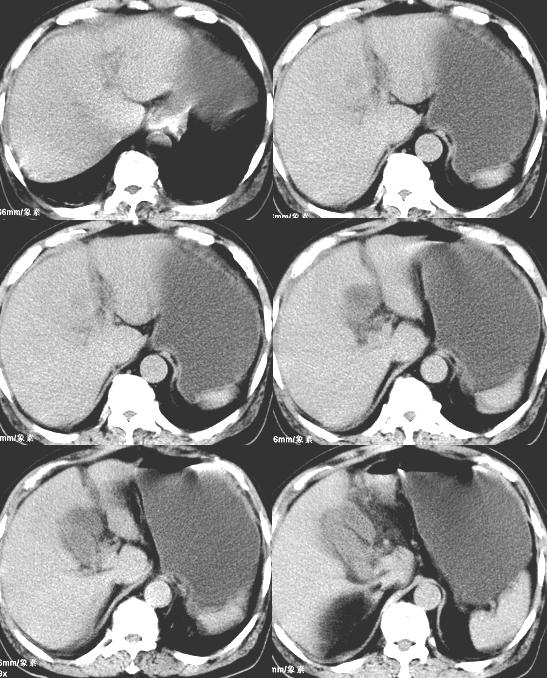

以下是引用liaoqiang在2008-3-27 15:57:00的发言:[br]1右肾脏周多发大小不一球形影,考虑肾脏囊肿可能性大。2胆囊边界欠清楚。考虑胆囊炎可能性。

以下是引用随光逐影在2008-3-27 16:33:00的发言:[br]考虑为:1)双肾囊肿可能。2)急性胆囊炎。建议:行进一步检查。